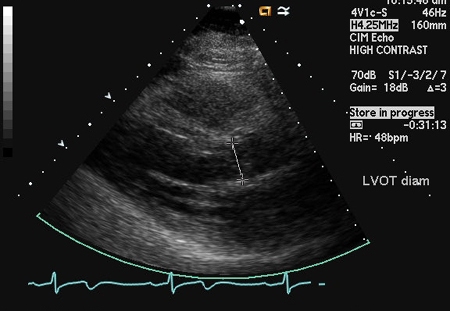

Parasternal long-axis view demonstrating left ventricular outflow tract diameter

From the collections of Dr Sanjeev Wasson and Dr Nishant Kalra; used with permission